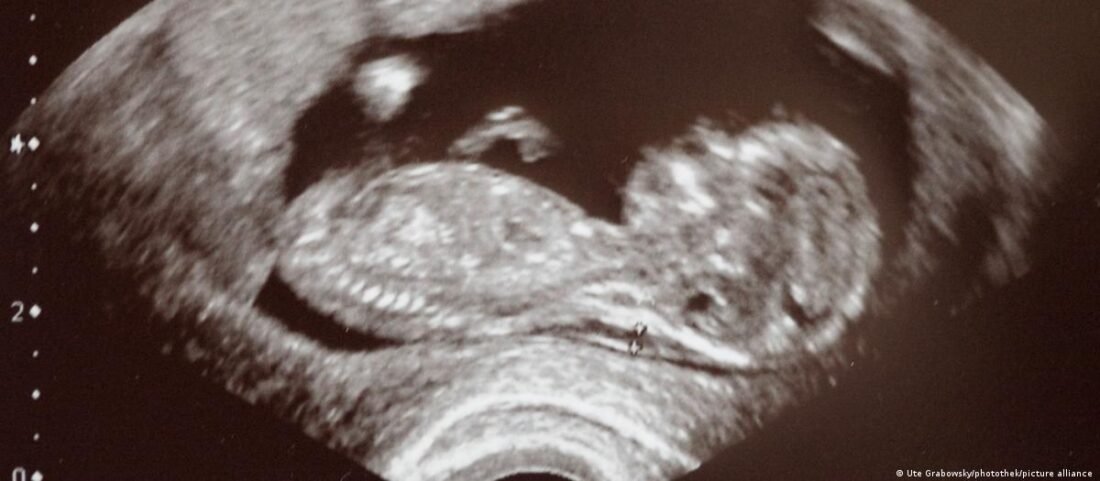

En un estudio publicado en Nature Communications, un equipo de investigadores del Campus Médico Anschutz de la Universidad de Colorado reveló hallazgos preocupantes sobre el impacto del consumo de antidepresivos durante el embarazo. Según la investigación, hecha con ratones, el uso de estos medicamentos puede afectar negativamente el desarrollo cerebral de los niños y aumentar significativamente el riesgo de trastornos mentales en etapas posteriores de la vida, consignó DW Español. Los científicos se centraron en el análisis de la fluoxetina, un compuesto activo en medicamentos ampliamente recetados como Prozac y Sarafem, destinados a tratar la depresión y la depresión posparto. La fluoxetina aumenta los niveles de serotonina en el cerebro, por lo que el equipo analizó su efecto en el desarrollo del córtex prefrontal del feto. EFECTOS PERJUDICIALES Won Chan Oh, autor del estudio y miembro del equipo de investigación en CU Anschutz, subraya la importancia de la serotonina en el desarrollo cerebral, pero advierte sobre los efectos desconocidos de su desregulación, especialmente en el córtex prefrontal. “Aunque se sabe que la serotonina interviene en el desarrollo del cerebro, los mecanismos responsables de esta influencia, concretamente en el córtex prefrontal, no están claros”, explica Oh. El estudio descubrió que la fluoxetina, al cruzar la barrera placentaria y pasar a la leche materna, puede influir directamente en las conexiones sinápticas del cerebro en desarrollo. Los resultados en modelos con ratones indican que tanto la deficiencia como el exceso de serotonina pueden alterar el desarrollo cerebral, afectando la capacidad del cerebro para aprender y adaptarse. LLAMADO DE ATENCIÓN Los investigadores enfatizan la importancia de que los profesionales de la salud participen activamente en la toma de decisiones relacionadas con la atención prenatal, equilibrando los beneficios con los riesgos potenciales de estas intervenciones. El equipo de CU Anschutz planea continuar su investigación, centrándose ahora en el impacto de la fluoxetina en el cerebro adolescente, en un esfuerzo por comprender mejor las implicaciones a largo plazo del tratamiento antidepresivo durante etapas críticas del desarrollo. (Foto: Tomada de DW Español) Compartir Navegación de entradas Una mala ventilación en el hogar impacta a tu salud Después de los 40 años, el cerebro sufre un gran “recableado”